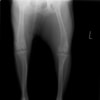

術前正面像

術前のTPAは左後肢33.1°右後肢26.8°でしたがTPLO実施により左後肢5.5°右後肢12°に矯正されました。